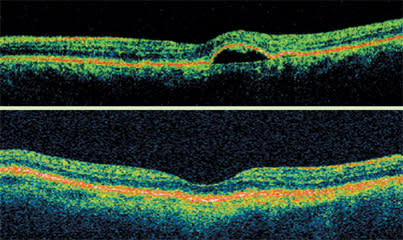

As a retinal specialist, I use the Stratus OCT in AMD to determine if fluid is present in the retina. That tells me if the disease is active and requires additional treatment or if I can simply continue to follow a patient. This is especially true in the case of anti-VEGF therapies.

The Stratus OCT continued to detect AMD disease activity after the patient was treated with PDT and bevacizumab. After one injection of ranibizumab, OCT showed a normal retinal appearance and vision improved to 20/30.

According to what is emerging as the standard practice, I re-treat whenever any one of the following criteria is met since the patient's last visit:

■ Decreased vision with increase in retinal thickness

■ Increased retinal thickness > 100 μm

■ Increase in cystoid spaces

■ Increased subretinal/sub-RPE fluid.